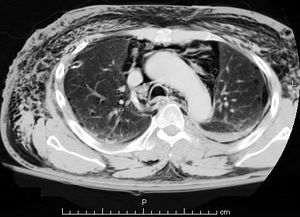

- CT Chest (preferred diagnostic test)

- AP/PA - Ring around right pulmonary artery, air along left heart border, air in upper chest/neck soft tissue

- Lateral - air along anterior heart border